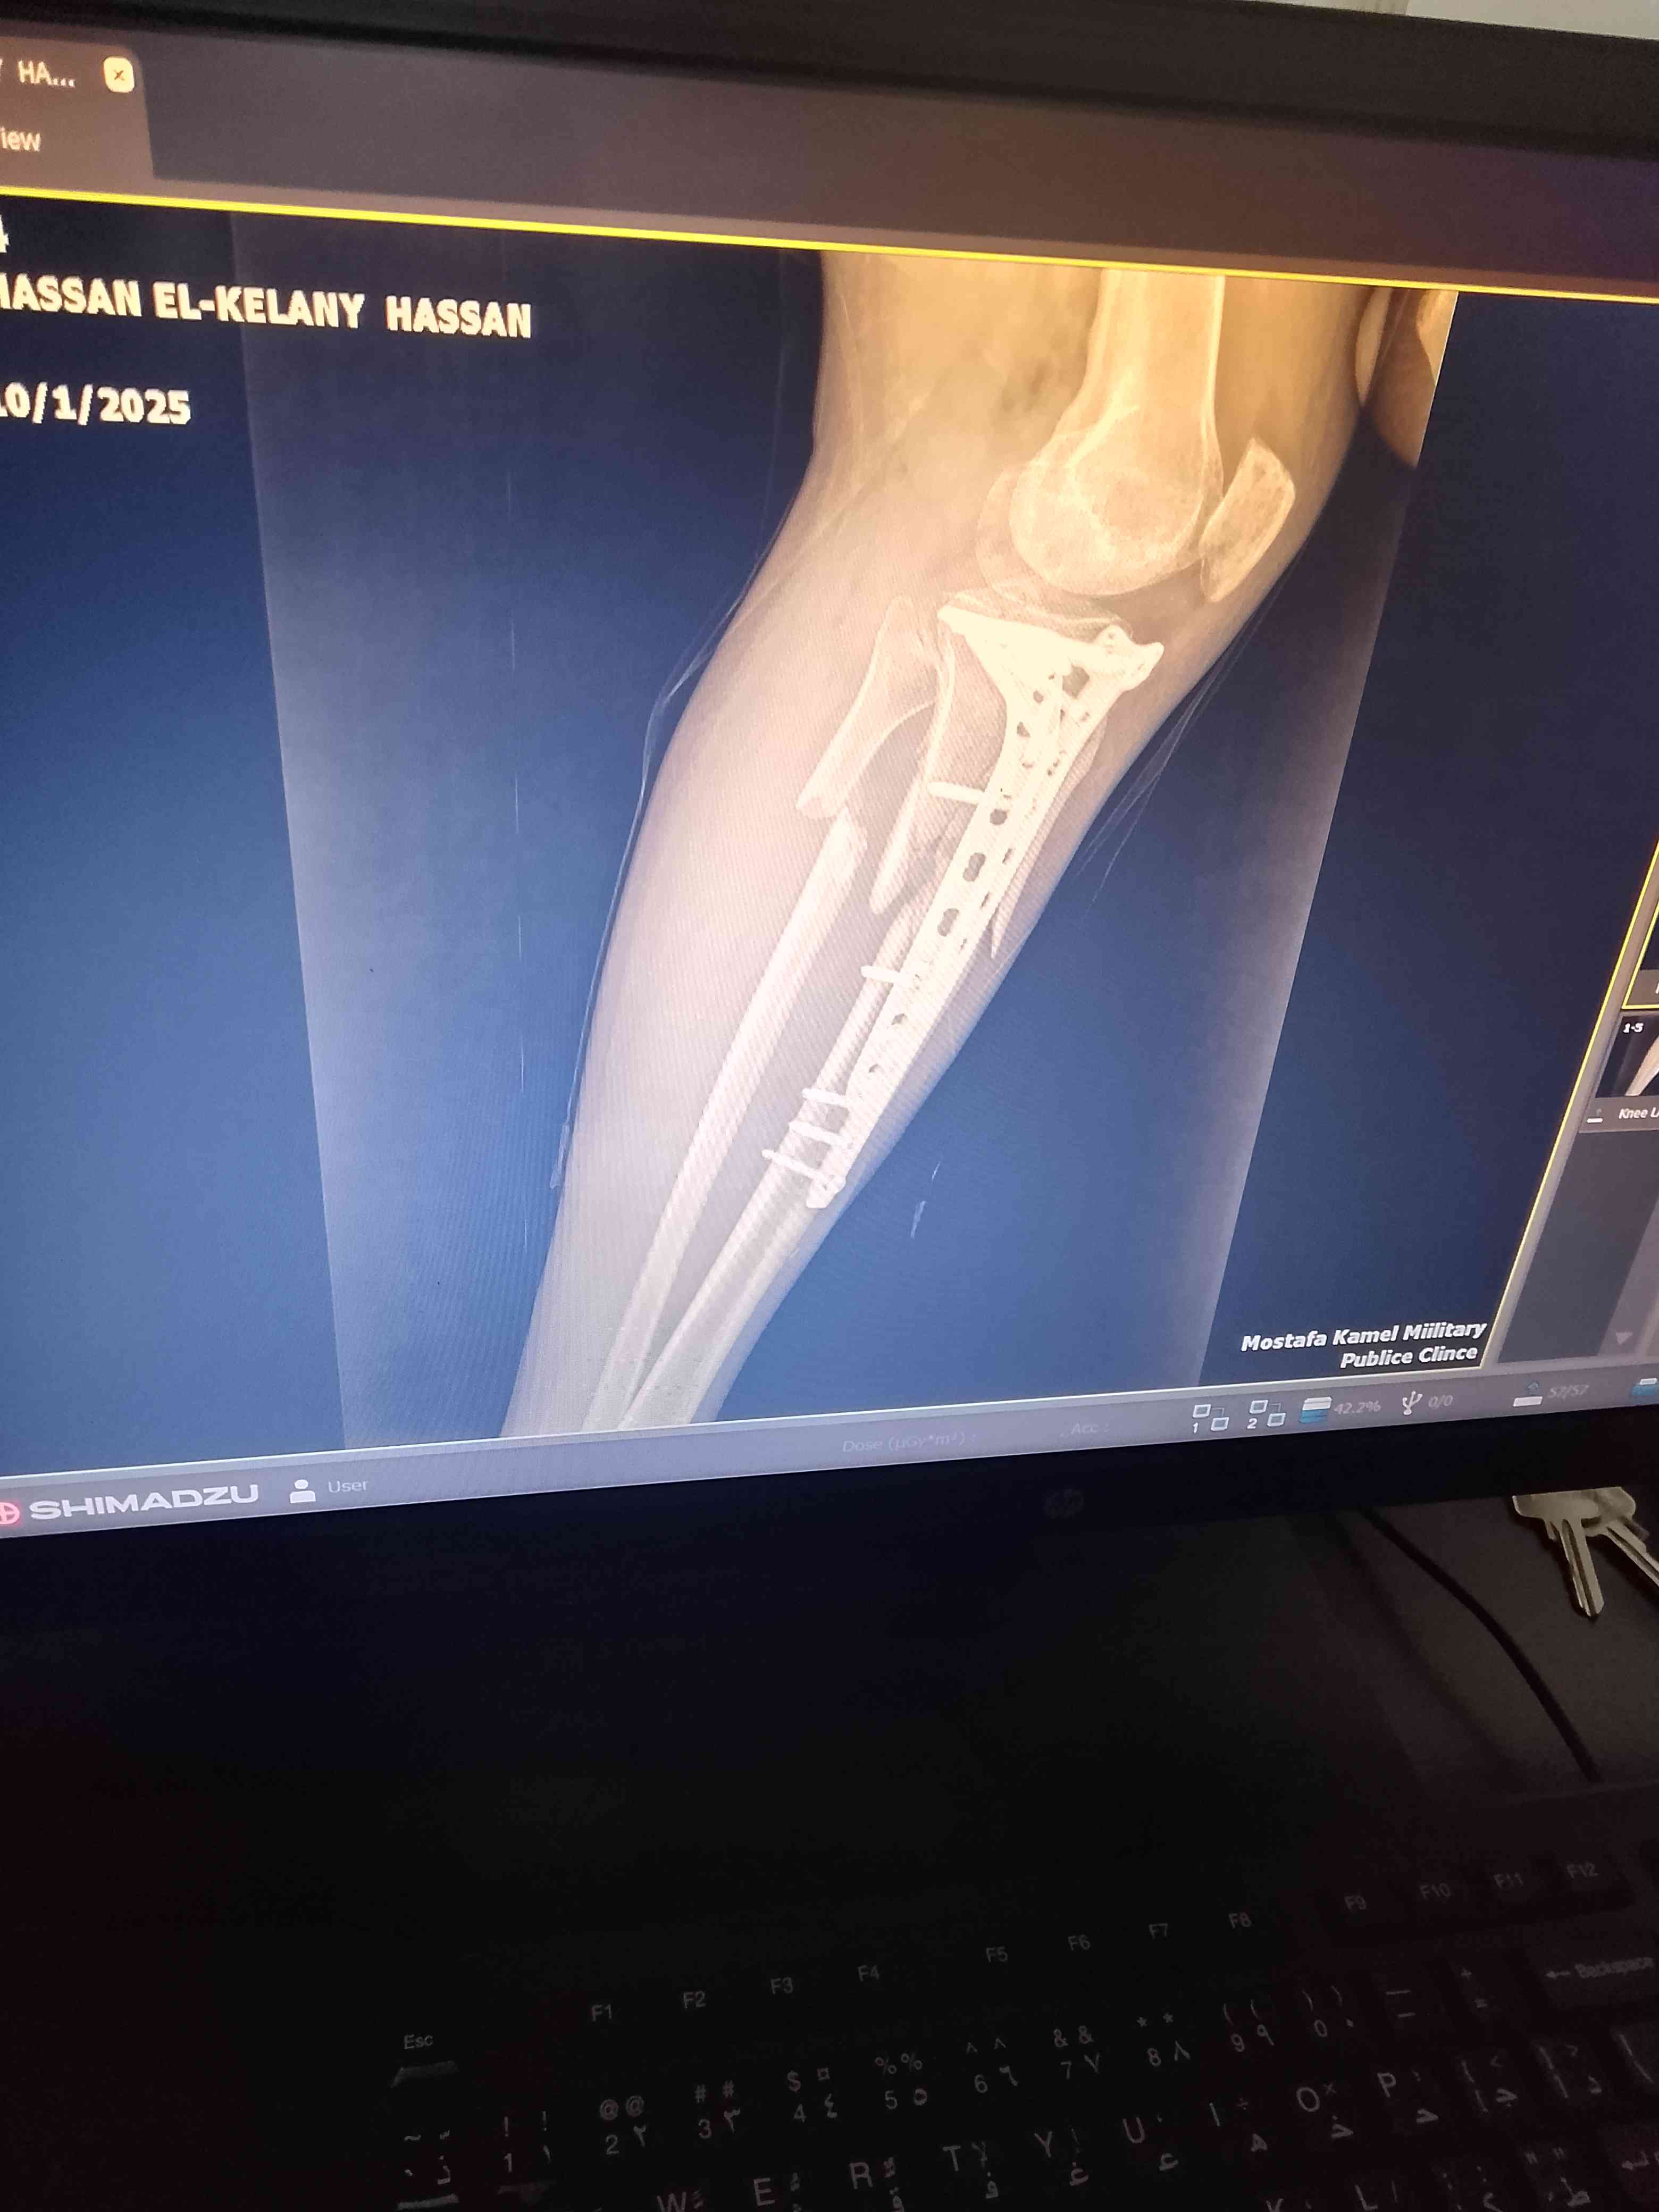

كسر عظام فى ساق الرجل اليسرى